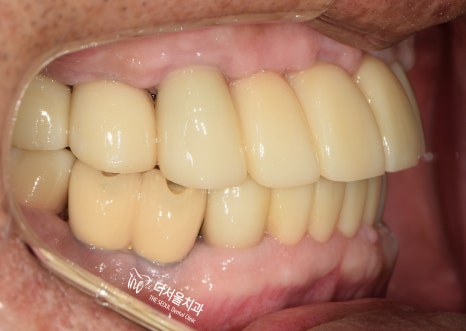

6. 최종 결과

완성된 보철을 전달받은 뒤,

그렇게 최종 보철을 세팅하며

꼼꼼하게 조정하고 마무리 지었는데요.

실제로 적용된 모습을 보면,

이전에 있던 진짜 치아랑 별반 다를게 없죠?

기능, 심미성 모두 신경써서

만들어드렸습니다.